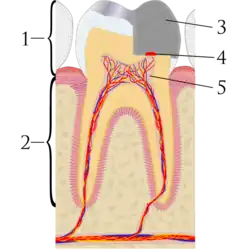

Pulp capping is a technique used in dental restorations to protect the dental pulp, after it has been exposed, or nearly exposed during a cavity preparation, from a traumatic injury, or by a deep cavity that reaches the center of the tooth, causing the pulp to die.[1] Exposure of the pulp causes pulpitis (an inflammation which can become irreversible, leading to pain and pulp necrosis, and necessitating either root canal treatment or extraction).[1] The ultimate goal of pulp capping or stepwise caries removal is to protect a healthy (or reversibly inflammed) dental pulp, and avoid the need for root canal therapy.

When dental caries is removed from a tooth, all or most of the infected and softened enamel and dentin are removed. This can lead to the pulp of the tooth either being exposed or nearly exposed.[1] To prevent the pulp from deteriorating when a dental restoration gets near the pulp, the dentist will place a small amount of a sedative dressing, such as calcium hydroxide or mineral trioxide aggregate (MTA). These materials protect the pulp from noxious agents (heat, cold, bacteria) and stimulate the cell-rich zone of the pulp to lay down a bridge of reparative dentin. Dentin formation usually starts within 30 days of the pulp capping (there can be a delay in onset of dentin formation if the odontoblasts of the pulp are injured during cavity removal) and is largely completed by 130 days.[2]: 491–494

Two different types of pulp cap are distinguished. In direct pulp capping, the protective dressing is placed directly over an exposed pulp; and in indirect pulp capping, a thin layer of softened dentin, that if removed would expose the pulp, is left in place and the protective dressing is placed on top.[4] A direct pulp cap is a one-stage procedure, whereas a stepwise caries removal is a two-stage procedure over about six months.